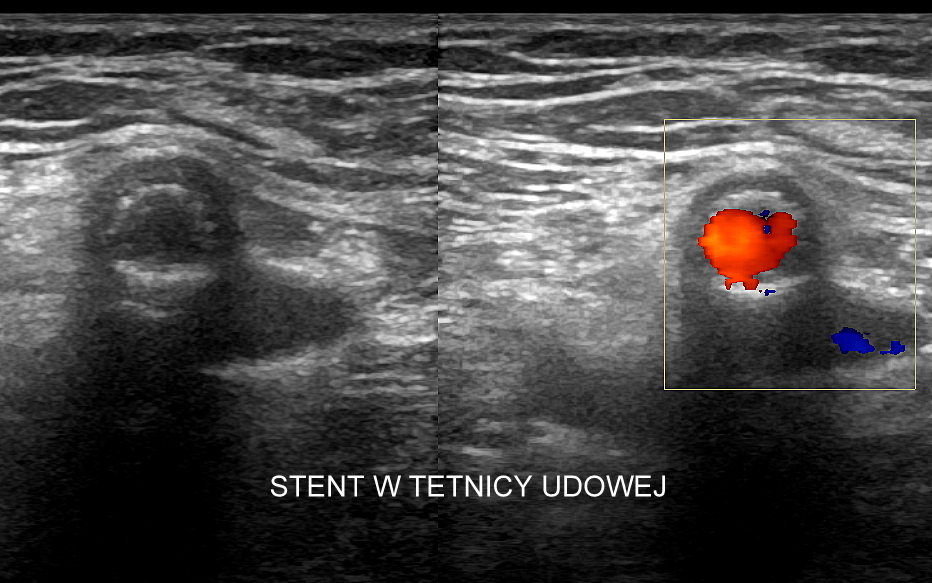

USG tętnic kończyn dolnych

Badanie USG Doppler tętnic, klasyczne badanie angiograficzne oraz badanie angio-TK to podstawowe i uzupełniające się metody diagnostyczne naczyń. Badanie dopplerowskie w przeciwieństwie do dwóch pozostałych jest metodą oceny funkcjonalnej a nie tylko wizualnej, tzn. oprócz stopnia zwężenia tętnicy ocenia również zaburzenia przepływu w oraz za zwężeniem, a także zaburzenia ukrwienia dystalnego tkanek.

Badanie USG Doppler tętnic kończyn dolnych wykonywane jest najczęściej w ramach diagnostyki miażdżycy zarostowej tętnic kończyn i jej objawów w postaci chromania przestankowego, czyli bolesności łydek, rzadziej ud i pośladków, pojawiających się w trakcie wysiłku fizycznego. Inne wskazania do USG tętnic kończyn dolnych obejmują uczucie chłodnych stóp, marznięcie nóg, diagnostykę zespołu zespół  Raynauda, czy choroby Buergera. W stanach nagłych badanie wykonuje się w przypadku ostrego niedokrwienia np. na tle obwodowej zatorowości tętniczej. Rzadsze patologie, które pojawiają się w obrębie tętnic kończyn dolnych to tętniaki prawdziwe, tętniaki rzekome (pseudotętniaki) i rozwarstwienia. Tętniaki rzekome są zwykle efektem powikłań jatrogennych nakłuć, a rozwarstwienia wynikiem urazów tętnicy, np. podczas uprawiania sportu.

Podczas wykonywania USG Doppler kończyn dolnych bada się osie tętnicze obu kończyn, które obejmują takie tętnice jak tętnica udowa wspólna, powierzchowna, głęboka, podkolanowa, tętnica piszczelowa przednia, tylna i tętnica strzałkowa. Ocenia się również ewentualne zwężenia oraz tzw. krążenie oboczne; poszukuje się cech zatorowości, zapalenia, rozwarstwienia i cech tętniaków.